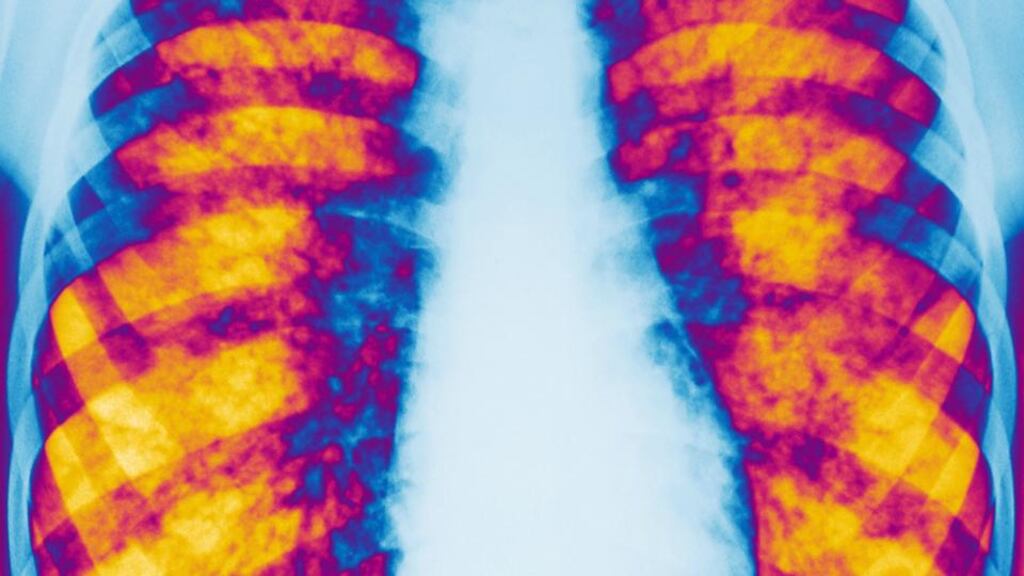

Cystic fibrosis affects more than 70,000 people worldwide, with some 90 per cent dying prematurely from respiratory infections caused by a multitude of infective and potentially resistant microorganisms.